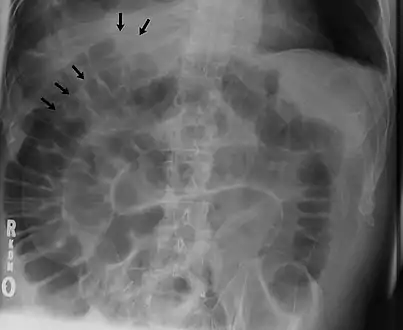

Signs that can be seen on projectional radiography are shown below:

The double wall sign marks the presence of air on both sides of the intestine.[19] However, a false double wall sign can result from two loops of bowel being in contact with one another.[20] The sign is named after Leo George Rigler.[21] It is not the same as Rigler's triad.

Double wall sign. This is a secondary sign of pneumoperitoneum. Patient is supine, and air within the abdomen and lumen of the bowel accentuate both sides of the bowel wall.- Ultrasound finding of pneumoperitoneum known as "peritoneal stripe sign"[24]